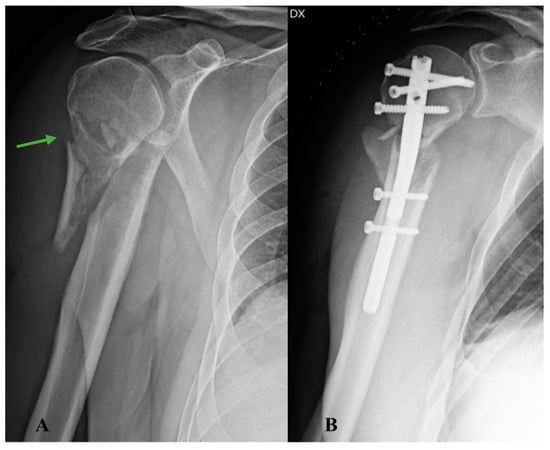

A 62-year-old male patient was taken to the emergency room of the Scientific Institute for Research, Hospitalization and Health Care (IRCCS) Galeazzi Orthopaedic Institute (Milan, Italy) for pain and functional impotence in the right shoulder following an accidental fall at home with direct trauma to the upper limb. During the anamnestic collection, the patient reported being affected by arterial hypertension and hypercholesterolemia. He also reported having suffered a previous ST-elevation myocardial infarction (STEMI), treated with drug-eluting stent implantation. The patient reported episodes of fever, weight loss, and asthenia in the year preceding the traumatic event. A shoulder radiograph with standard projections was performed, which allowed for the diagnosis of a humeral surgical neck fracture, classifiable as type 11-A2.2 according to the AO/OTA Fracture and Dislocation Classification revised in 2018 (Figure 1A). The results of routine blood tests performed on admission were normal. Two days after the traumatic event, the patient underwent surgery to reduce and fix the fracture with a T2 ® model 8 mm × 150 mm intramedullary nail and screws (Stryker, Kalamazoo, MI, USA) (Figure 1B) under general anaesthesia. The immediate postoperative course was regular, with good control of painful symptoms and reported subjective well-being. On the second postoperative day, the patient was discharged with indications for clinical follow-up (FU) and periodic radiographs.

Figure 1. Right shoulder X-rays: (A) anteroposterior radiograph of the shoulder showing a surgical neck fracture of the proximal humerus (arrow); (B) antero-posterior radiograph of the postoperative shoulder showing reduction of the major fracture fragments and fixation with T2 ® model 8 mm × 150 mm intramedullary nail and screws (Stryker, Kalamazoo, MI, USA).